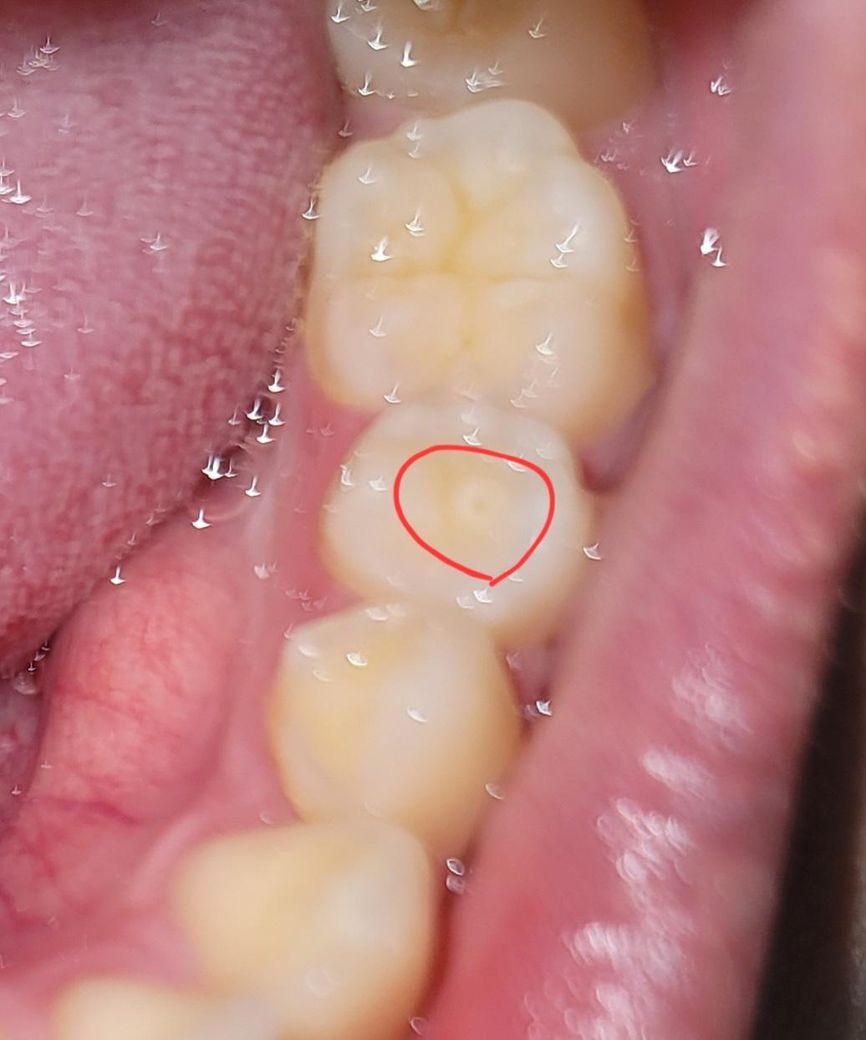

사진처럼 하얀색으로 구멍이 있는데 충치인가요?

딱딱한 음식을 씹다가 한번 확 아프고 그 뒤로 계속 이쪽으로 씹으면 신경이 아픈것 같은 통증이 있습니다. 그러다가 또 하루이틀 지나면 씹을때 통증이 사라지고 아무렇지도 않은데 다시 딱딱한 음식을 이쪽으로 씹으면 또 반복입니다. 사진을 찍었을때는 저렇게 흰색으로 구멍이 보이는데 충치인가요?

사진상으로 보아서는 정확히 알 수 없으나 초기 충치 정도로 보입니다. 다만 해당 치아는 치외치나 치내치일 가능성이 큽니다. 이러한 경우에는 조금만 구멍이 있더라도 신경과 상대적으로 가까워서 시린 증상이나 통증이 나타날 수 있습니다.

사진에 보이는 건 치외치인거 같습니다. 치외치부분이 사용하면서 교모되서 생긴겁니다. 충치는 아닙니다.

치외치로 보입니다 치외치의 뿔 부분이 파절되면서 치아 속 신경이 노출되어 통증이 있는 것입니다 신경치료 또는 치수절단술이 필요합니다